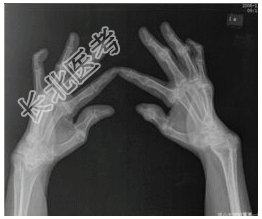

- [材料题] 患者女,55岁,全身多处关节肿痛30余年。查体:双手关节多处变形,晨僵,类风湿因子阳性。行双手正斜位片检查。

- 简答题1、患者的诊断及依据是什么?

- 简答题2、鉴别诊断是什么?